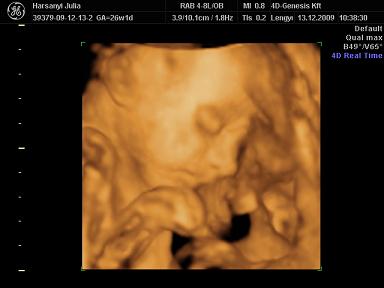

Reggel 10-re mentünk a genesisbe UH-ra. Szuper volt! :) Persze Szonja megint szégyenlősködött, és az arcát nem akarta annyira mutatni, de azért sikerült egy picit elkapni. De amit művelt, ez fantasztikus volt! Tudni kell a családunkról, hogy nálunk mindenki kéjenc, ami annyit jelent, hogy mindenkit egyfolytában simogatni, masszírozni kell (kutyát macskát beleértve, de főleg páromat meg engem). Na, a kislányunk sem hazudtolta meg a vérét, ő is ilyen! Befeküdt az UH fejnek háttal, és kifejezetten lehetett rajta látni, hogy nyomja a kis hátát meg fenekét, attól függően hogy hol szeretné magát massziroztatni. Teljesen ellazult, volt, hogy be is aludt, annyira édes volt :) A szonográfus nőnek is nagyon tetszett :) Azt mondta, teljesen tökéletes, gyönyörű baba, és természetesen mi is így láttuk :) A mérete pont a korának megfelelő, 850g, a talpacskája már majdnem 5 cm :) Ha így haladunk, akkor teljesen jó súllyal (3300 gr) fog születni.

Julcsi,teszel fel 4D fotókat Szonjáról a kis kéjenckédről? :)

Na próbálok feltenni képet a kis Tündérről: